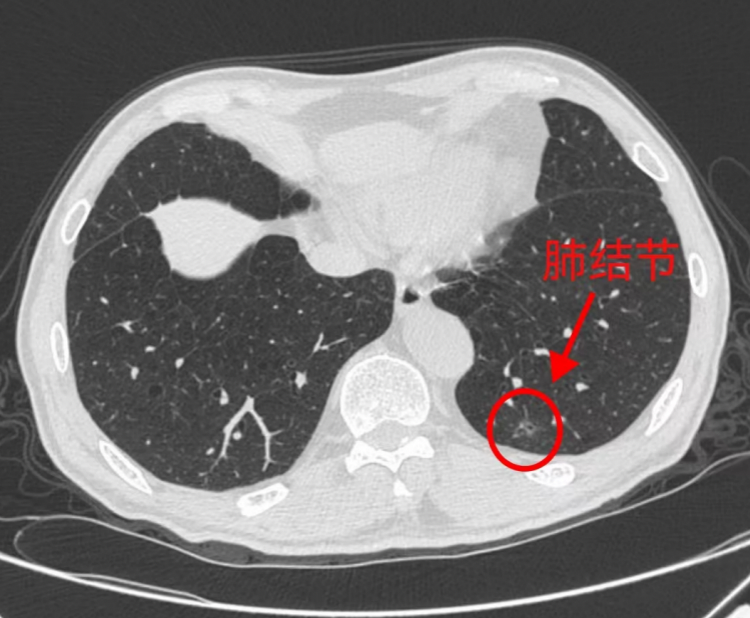

在体检中越来越多的肺小结节被发现,是良性还是恶性?如果评估是早期肺癌,可能需要进行肺结节微创手术。但是,由于这些结节体积较小、密度低,病变离胸膜较远,往往不能通过肉眼观察或通过术中探查触及肿物,导致难以精准切除。据记者了解,广州市第一人民医院胸外科引进了针对此类结节的“高科技”,可助力精准切除肺结节。

近日,28岁的刘女士在做体检时,通过胸部CT发现了一个8mm的肺小结节。在广州市第一人民医院经会诊评估后,考虑倾向早期肺癌可能性较大,医生建议进行手术治疗。

由于刘女士的肺结节体积较小,仅为8mm,且密度低,病变离胸膜较远,这种小结节的手术定位给胸外科医生带来了巨大挑战,传统手术难以精准切除。

目前,由于体检中广泛应用低剂量螺旋CT使得很多肺小结节被发现,一旦评估为早期肺癌的时候,常常建议尽早手术切除。

普通CT图像